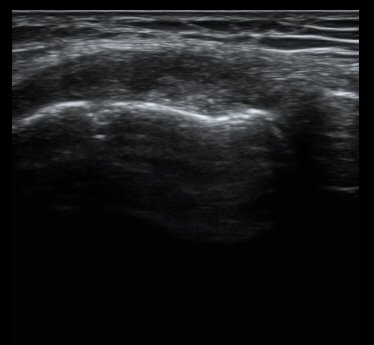

´ëÅð°ñ ¿ÜÃø°ú ¾ÕÂÊ Á¾´Ü¸é°Ë»ç¿¡¼­ ¾à°£ÀÇ ¼ö¾×Àú·ù°¡ °üÂûµÊ(±×¸² 1, 2).

¹«¸­ ³»ÃøºÎÀδë Á¾´Ü¸é°Ë»ç¿¡¼­ ³»ÃøºÎÀδë Ç¥Ãþ±ÙÀ§ºÎ Àú¿¡ÄÚ ºÎÁ¾ ¹× ½ÉÃþ±ÙÀ§ºÎ ºÎºÐÆÄ¿­ÀÌ

°üÂûµÊ(±×¸² 3, 4).